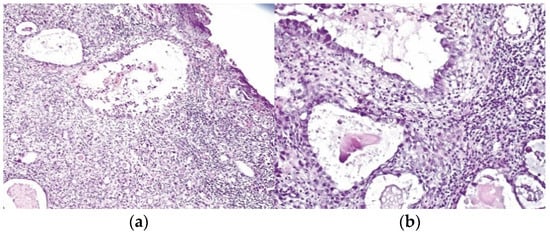

| LEEP | atypical mesonephric hyperplasia with a malignant transformation zone—mesonephric adeno-carcinoma with moderate cell pleomorphism, moderate mitotic activity, without invasion of the lymphovascular space, resection limits tangential to the lesion |

| Radical vaginal trachelectomy with laparoscopic pelvic lymphadenectomy | Uterine isthmus—endocervix—upper limit of resection with benign mesonephric hyperplasia with areas of atypical mesonephric hyperplasia, showing moderate atypia; |

| Cervix with previous conization –appearance of atypical mesonephric hyperplasia; zone of stromal invasion and malignant transformation—endocervical mesonephric adenocarcinoma with moderate cell pleomorphism and mitotic activity, intraluminal detritus, added inflammation | |

| Right ilioobturator lymphadenctomy specimen—eleven lymphonodules with sinus histiocytosis, lipomatosis, no tumor metastasis; left ilioouturator lymphadenctomy specimen—seven lymphonodules with sinus histiocytosis, lipomatosis, no tumor metastasis. The stage according to FIGO classification was pT1b1 N0 Mx. | |